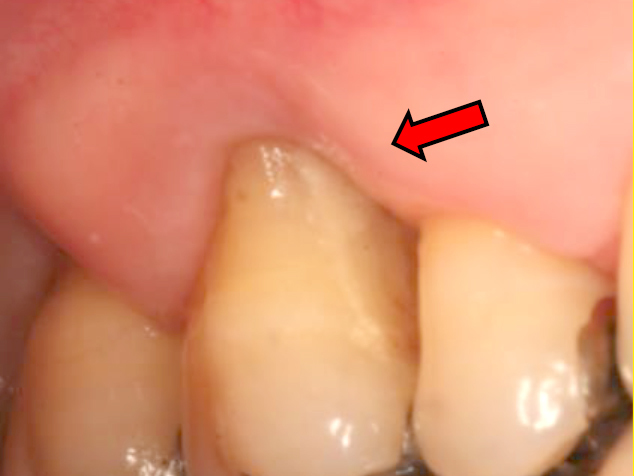

再生療法を行なった処置

Before

After

初診時年齢:30代女性

治療:歯周病治療

治療法:歯周組織再生療法

治療期間:1ヶ月

費用:110,000円(税込)

リスク・副作用:歯周外科処置後に出血、腫れ、あざが出ることがありますが時間とともに治ります。術後3週間程度噛んだときの痛みや歯が浮いた感じがすることがあります。